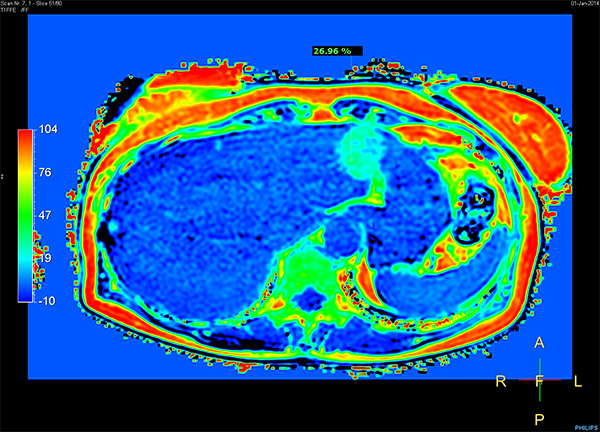

Patient with multiple liver lesions showing up hyperintense on T2-weighted images. The high spatial resolution of MultiVane XD can be appreciated by comparing the images demonstrating the two hyperintense focal liver lesions. mDIXON Quant was performed for quantification of intralesional and hepatic parenchymal fat content. The fat content in the liver parenchyma was normal. The lesion has a fat fraction of 25-30%. Histopathologic diagnosis was hepatocellular adenoma.